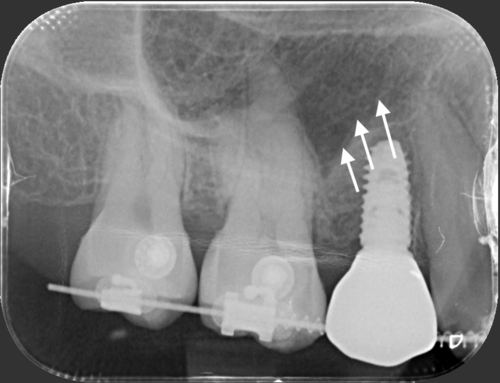

Even a perfectly placed implant can look artificial if the surrounding gums aren’t appropriately managed. Common issues with poor soft tissue management:

❌ Metal showing at the gumline

❌ Uneven gum heights

❌ Tissue recession

❌ Red or black tissue colour

❌ Unnatural contours

✅ Pink, healthy gums that match your natural teeth in color and texture

✅ Proper gum height and contours

✅ Prevents gum recession and metal show-through

✅ Natural look growing

✅ Protects implant from bacteria and bone loss

Getting your implant as soon as possible (after tooth loss) is the best way to reduce bone loss and avoid bone graft.

Bone loss happens immediately after you lose your teeth

Note: sinus floor will also drops down and further reduce available bone